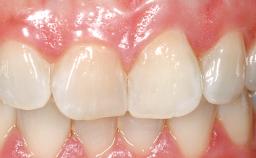

This 43-year-old male patient, a non-smoker, came to our practice because of a fracture of tooth 12 caused by a bicycle accident. Due to the combined para- and infrabony crown and root fracture, tooth extraction, and subsequent implant placement were suggested to the patient as the therapy of choice. The patient had high esthetic expectations with regard to the treatment outcome and asked for an immediate fixed provisional restoration. His individual esthetic risk profile summed up to a medium esthetic risk.

Patient's Esthetic Expectations Low Medium High

Lip Line No exposure of papillae Exposure of papillae Full exposure of mucosa margin

Periodontal Phenotype Low-scalloped, thick Medium-scalloped, medium-thick High-scalloped, thin